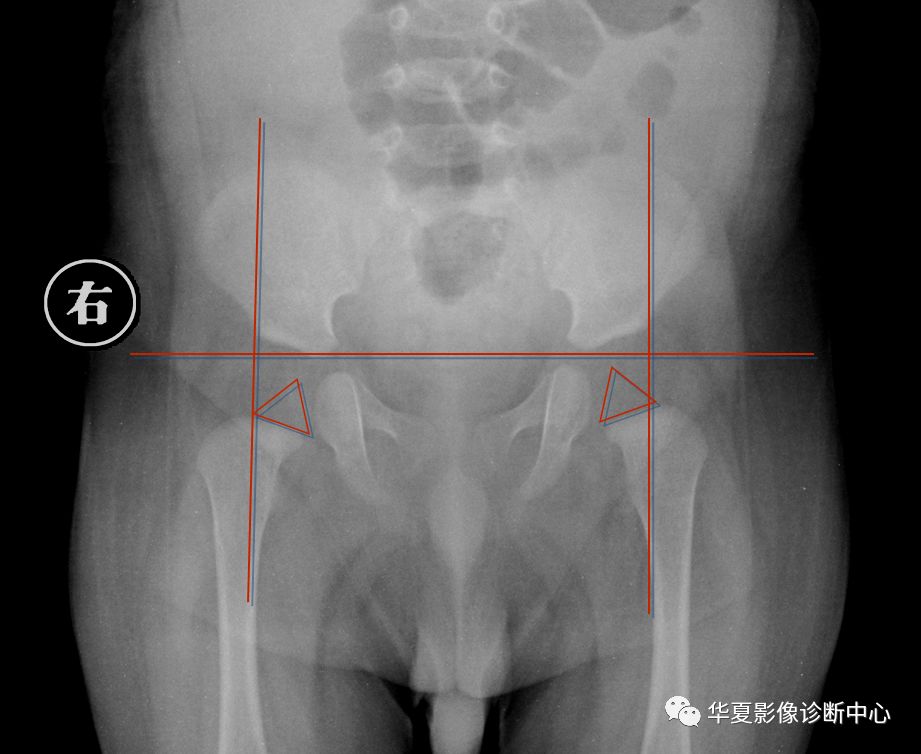

3.Perkin象限

当股骨头骨骺核出现后可利用Perkin象限,即两侧髋臼中心连一直线称为H线,再从髋臼外缘向H线做一垂线(P),将髋关节划分为四个象限,正常股骨头骨骺位于内下象限内。若在外下象限为半脱位,在外上象限为全脱位。

新生儿正常股骨上端鸟嘴状突起位于内下象限内。若在外下象限为半脱位,在外上象限为全脱位。